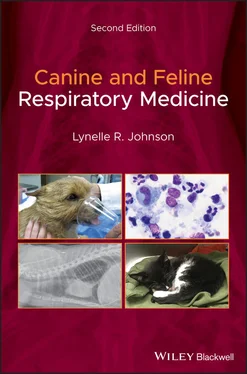

Figure 2.10 Image of the normal nasopharynx in (a) a dog and (b) a cat. The soft palate is dorsal in these images.